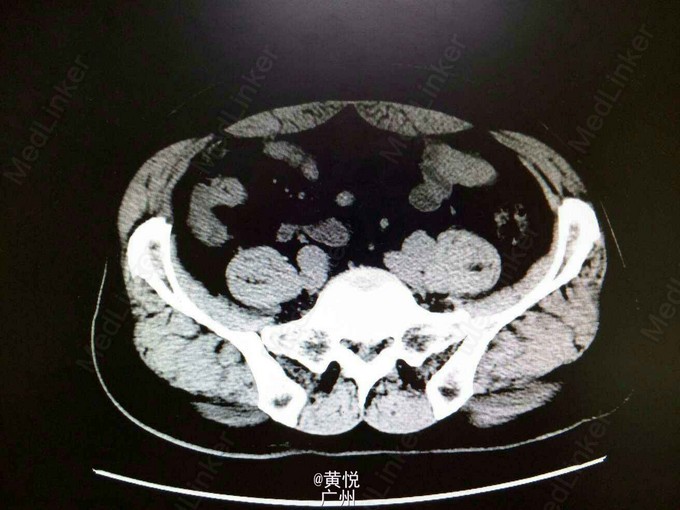

查体:生命体征平稳,屈曲体位,心肺无特殊,腹平软,右下腹麦氏点有压痛以及反跳痛,无腹部包块,双肾叩击痛(—)。辅助检查:血常规提示WBC 1.3*10^9;中性粒细胞 6.7*10^9,中性粒细胞比值正常;血生化未见异常。腹平片提示:小肠少许积气,考虑肠郁张;腹部CT检查提示结肠局部肠壁增厚并周围淋巴结增大,建议进一步检查,考虑右肾囊肿。